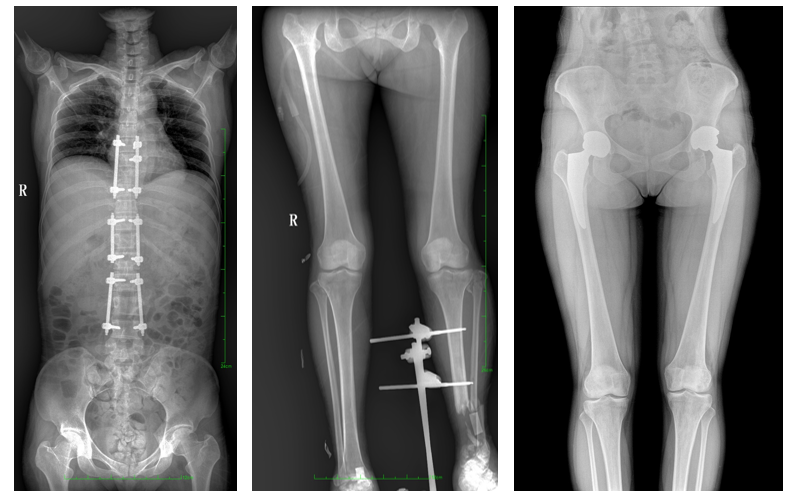

DR常用于人體胸部及骨骼攝片,也可拍攝其他部位,例如腹部、牙齒、頭顱等。使用人群較廣,可以進(jìn)行全身各部位檢查,曝光后幾秒就可獲得數(shù)字影像,成像速度快,且價(jià)格便宜,極大提高了工作效率,方便臨床重癥、急癥患者的診治。

站立位X線影像是測(cè)定人體負(fù)重骨骼的生物學(xué)力線、對(duì)稱結(jié)構(gòu)平滑線及脊柱側(cè)凸角等首選的檢查內(nèi)容,這和CT、MRI臥位成像,在臨床意義上有著根本區(qū)別。在脊柱及下肢的臨床治療過程中,一般需要進(jìn)行矯正和關(guān)節(jié)置換手術(shù)治療,在對(duì)其進(jìn)行手術(shù)前后,均需要拍攝站立位負(fù)重X光片以便分析病情,明確診斷和觀察治療效果。

常規(guī)DR拍攝面積有限,最大規(guī)格僅有43cm,但成人男性全脊柱長(zhǎng)度平均為70-75cm,女性為66-70cm,而雙下肢更長(zhǎng)。普愛醫(yī)療PLX8600動(dòng)態(tài)DR的43cm*86cm超大有效視野,可一次成像全脊柱及雙下肢。